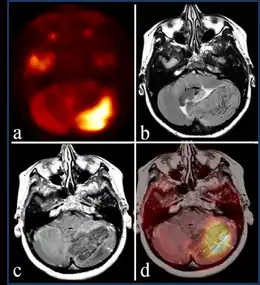

Diagnosis

The diagnosis of the condition Lhermitte–Duclos disease can be done via the following:[4]

- Magnetic resonance image

- Positron emission tomography